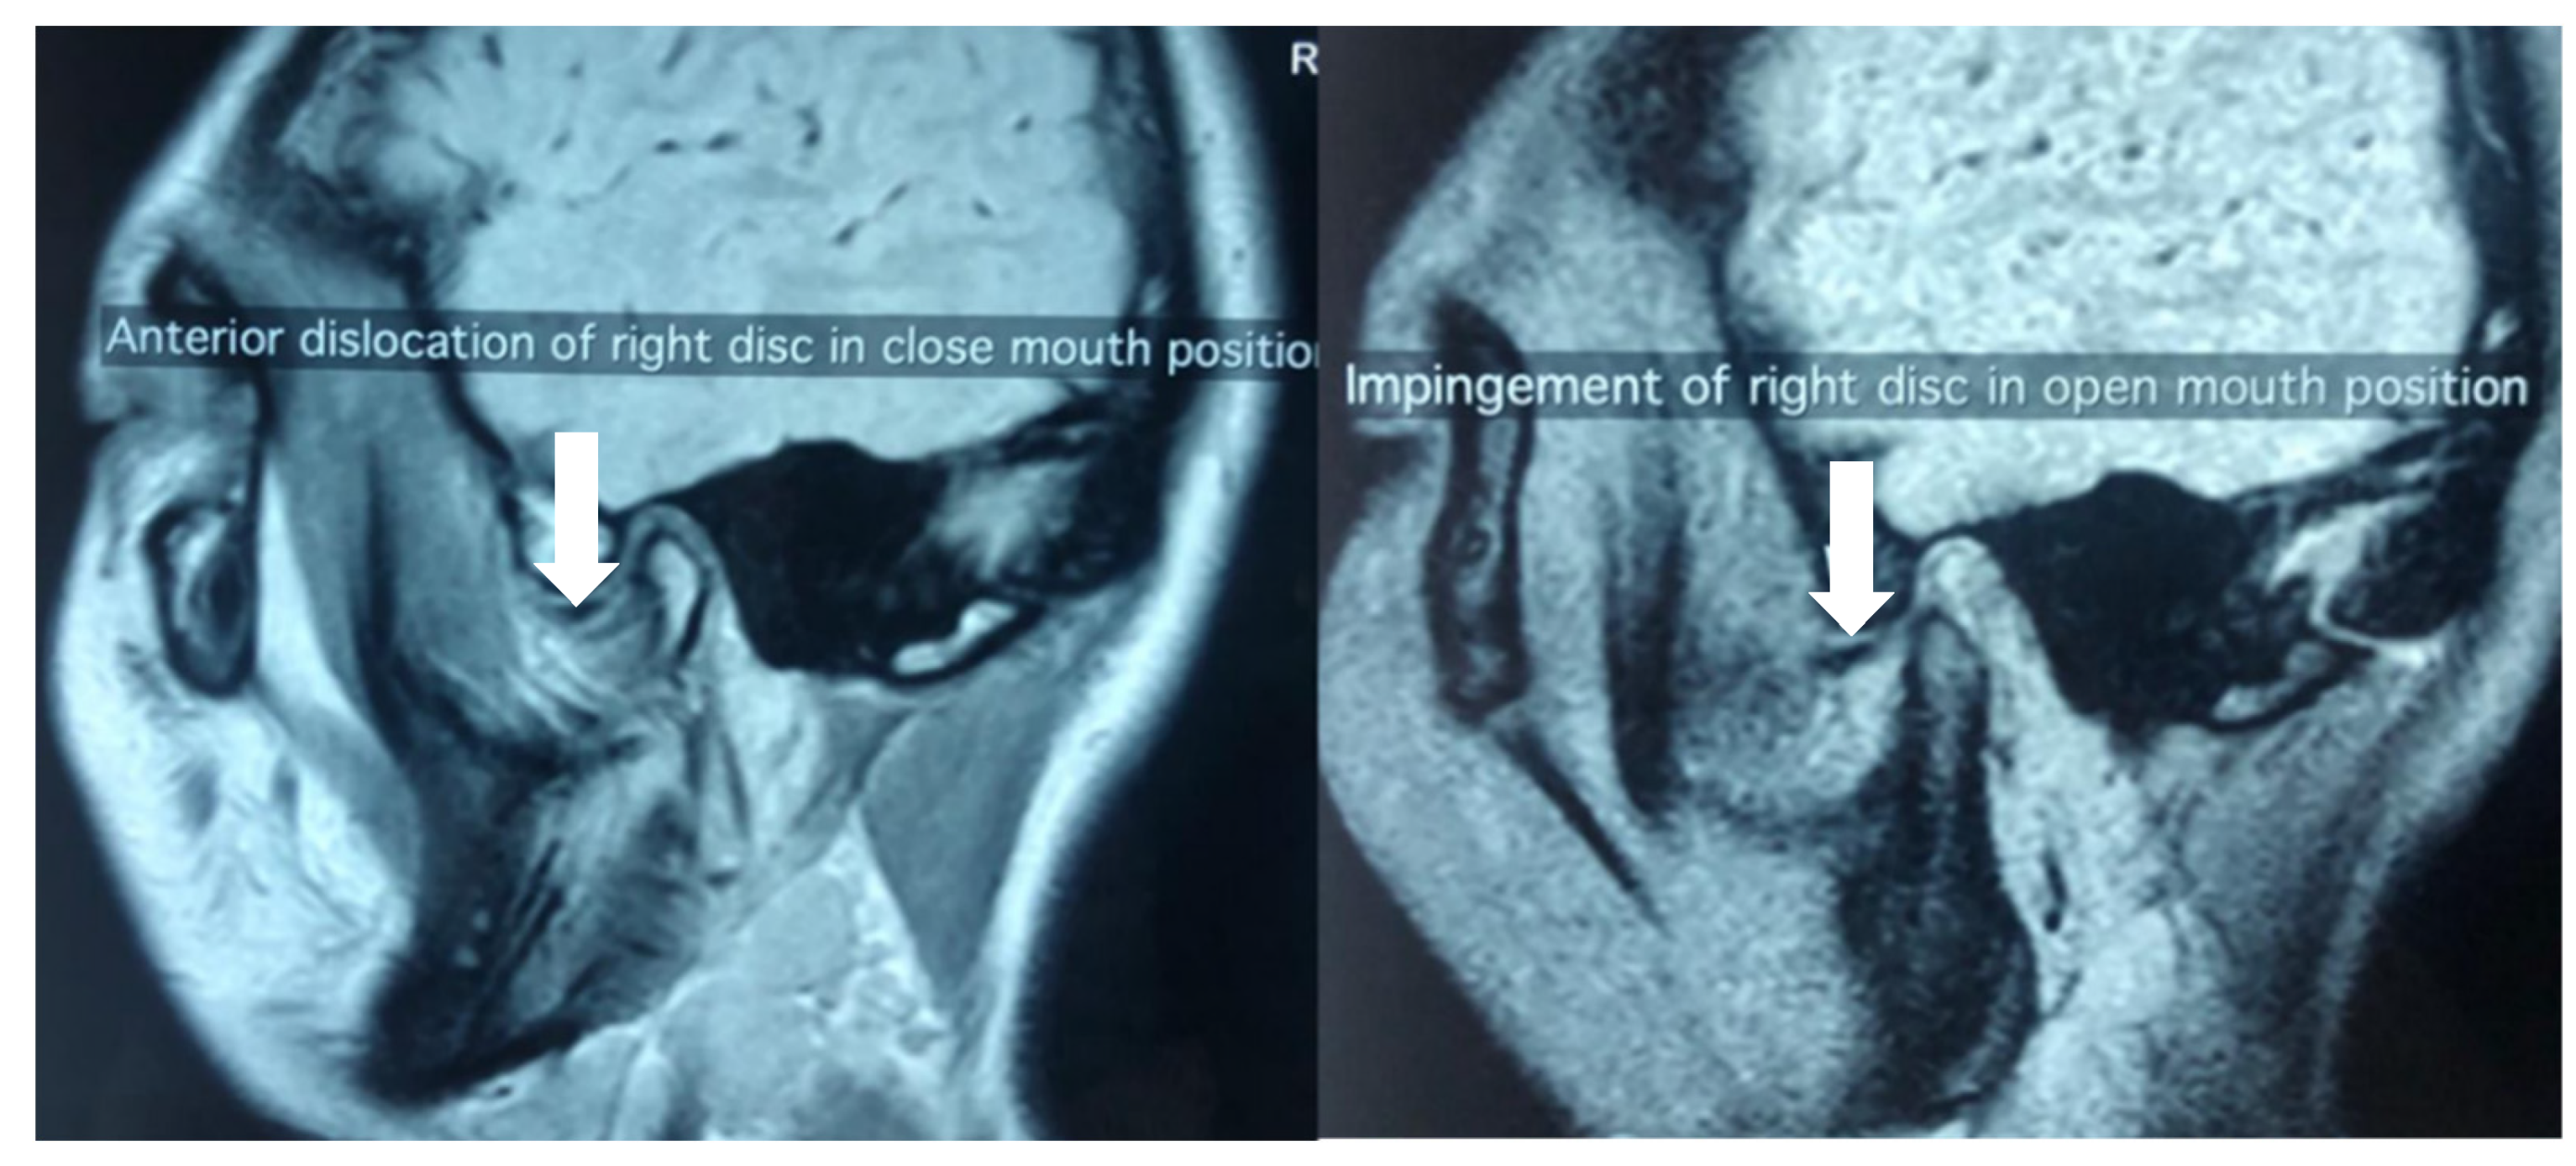

| Disc displacement with reduction | Clicking in the TMJ upon function |

| Disc displacement with reduction with intermittent locking | Clicking in the TMJ with reported episodes of limited mouth opening |

| Disc displacement without reduction with limited opening | Limited mouth opening affecting function, with maximum assisted opening < 40mm |

| Disc displacement without reduction without limited opening | Limited mouth opening affecting function, with maximum assisted opening of ≥ 40mm |